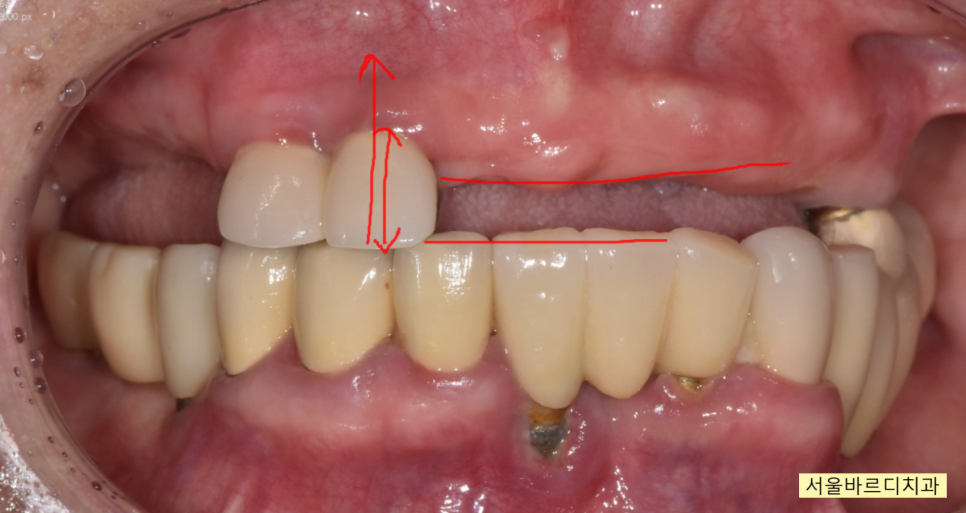

제일 불편한 입술을 씹는 문제를 해결하려면

치아 높이를 확보해주어야합니다.

현재 상황은 어금니 머리가

들어갈 공간이 나오지 않는 상황

(윗니와 아랫니가 거의 맞닿아있는 상태였죠.)

뽄을 뜨고 보철을 만드는 과정에서

위 아래 높이를 올려 마무리 하였습니다.

평소 위 아래 치아가 닿는게 있었기 때문에

높이를 올리게 되면

처음에는 물리는 느낌도 이상하고

어색어색한 것이지요.

치료가 끝난 모습입니다.

윗니가 아랫니를 덮는

정상적인 교합으로 마무리 되었습니다.

입술을 씹는 문제는

자연스럽게 해결~~